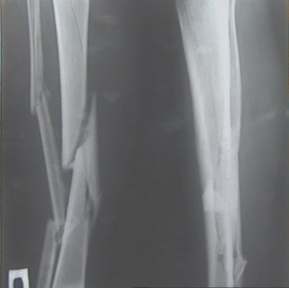

Re: Неправильно сросшийся перелом голени

Александр Николаевич, к сожалению больной не является на контрольные осмотры. Я последний раз видел больного, когда прошло 7 месяцев после операции БОС. У него все хорошо. Каких либо жалоб и ограничений в нагрузке нет. Высылаю снимки до операции и последние снимки.